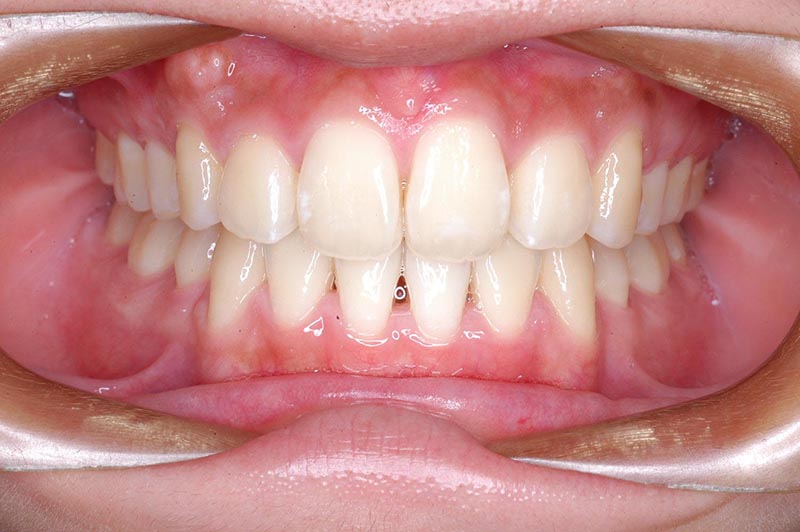

動的治療終了時

FP・IOP

批評・予后 上顎大臼歯のアンカーロスも生じず、大幅な前歯舌側移動、咬合の緊密化、歯根のパラレリングは行えた。上下口唇形態は改善し、良好なプロファイルが得られた。